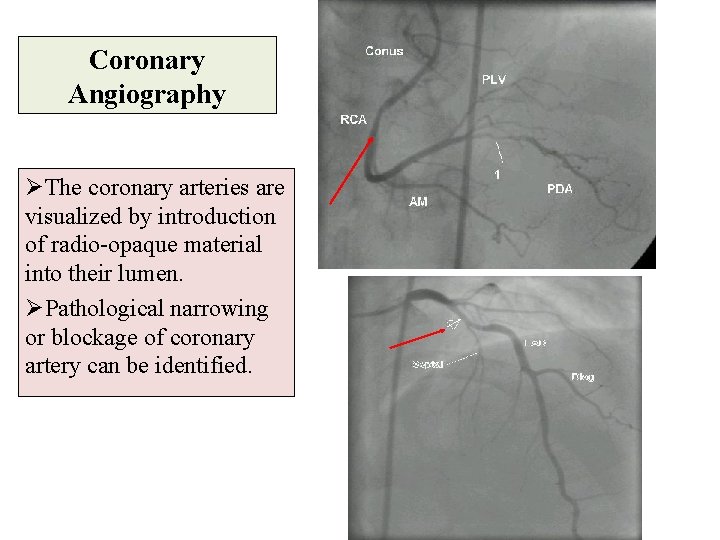

Coronary Angiography ØThe coronary arteries are visualized by introduction of radio-opaque material into their lumen. ØPathological narrowing or blockage of coronary artery can be identified.